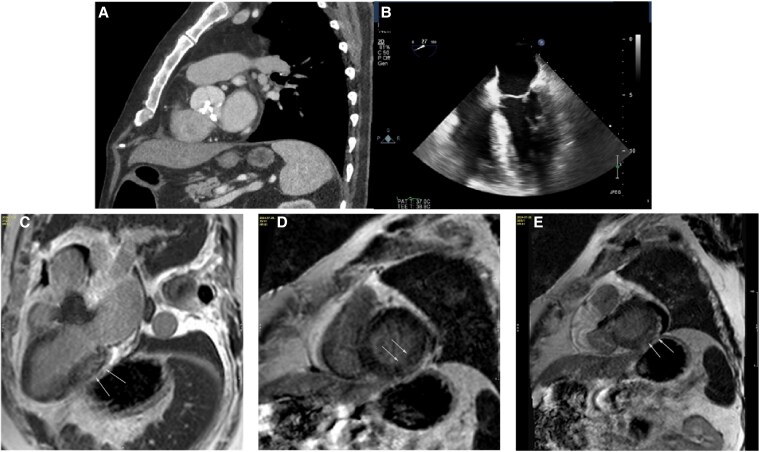

Case summary: We present a case of degenerative AS where the pathology analysis post-surgical replacement demonstrated amyloid deposits subsequently identified as AL subtype by mass spectrometry. Subsequent investigations demonstrated no myocardial or systemic involvement. Following multidisciplinary discussion, cardiac biopsy and chemotherapy were deferred given the isolated nature of aortic valve involvement and clinical stability.